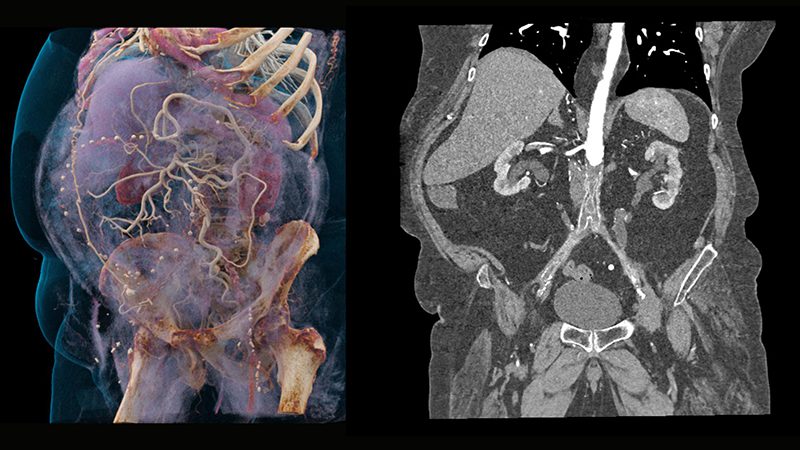

3D Görüntüleme

Kardiyak fonksiyonların değerlendirmelerini özel 3D görüntüleme tekniği ile yapıyoruz

• Böbrek taşlarının yapısının analizi, kalsiyum oksalat taşları görüntülemesi ve gut tofüsleri (şişlikleri) görüntülemesi,

• Böbrek yetmezliği ya da e-GFR değeri düşük hastalarda, çok düşük seviyede kontrast madde kullanarak renkli anjiyografi çekimleri,

• Metal uzaklaştırma programı ile protez ve implantların, kemik ve yumuşak dokudan ayrılması ve yumuşak dokuların daha optimal olarak değerlendirilmesi,

• Ca++ plaklarının görüntü üzerinden atılması,

• Sinematik 3D görüntülerin oluşturulmasıyla, cerrahi öncesi planlama ve değerlendirmenin yapay gerçeklikle değerlendirilmesi,